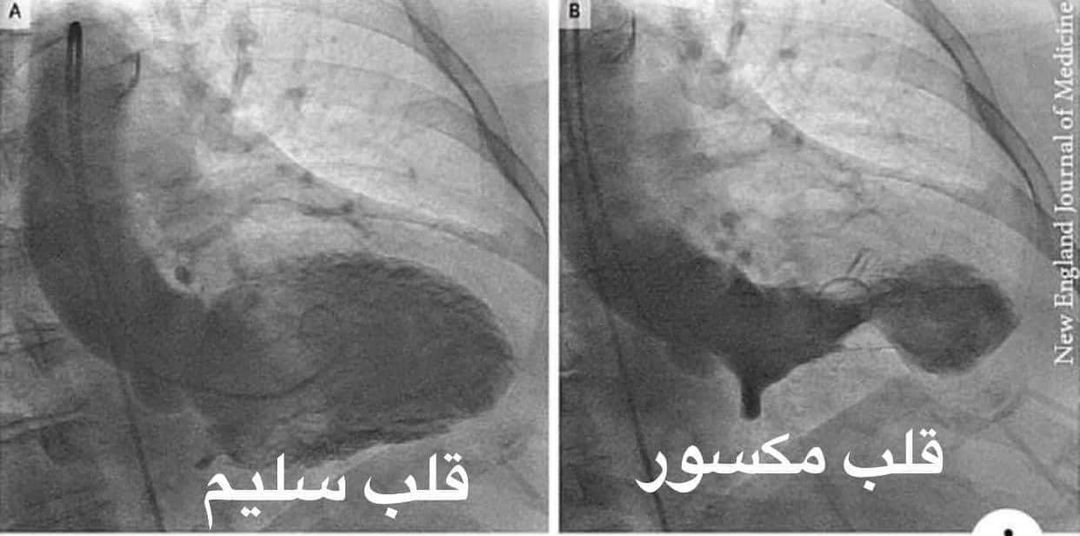

القلب المكسور والقلب السليم

أضاف، أستاذ أمراض القلب، وعميد المعهد القومي للقلب سابقًا، أن هناك حالات إكلينيكية واقعية نشهدها، "لقلوب مكسورة" موضحًّا في صور نشرها على صفحته الشخصية في فيسبوك لقلوب، قائلًا: "القلب اللي ع اليمين في الصورة قلب مكسور، شايفينه ضعيف وانكمش ازاي، والقلب اللي على الشمال قلب سليم شايفينه محتفظ بقوامه وشكله ووظيفته ازاي".

يظهر القلب مثل البالون، لافتًا إلى أن العلماء وصفوا هذه الحالة بمتلازم القلوب المنكسرة، وهي منكسرة عاطفيًا وعضويًا "Broken heart syndrome".